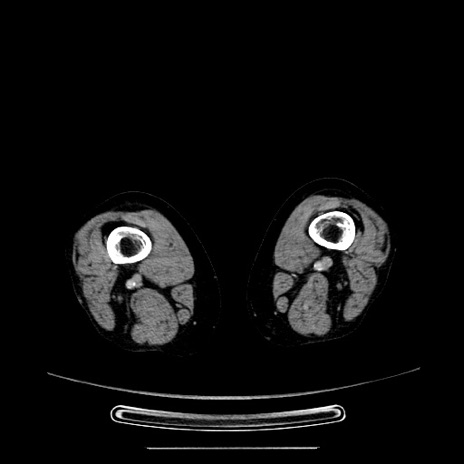

症例5(横断像)

【症例】70歳代女性

【主訴】お腹が張る

【現病歴】1週間くらい前から腹部膨満の自覚あり。昨日夜から増悪したため、本日救急外来受診。

【身体所見】意識清明、BT 36.5℃、BP 165/106mmHg、HR 80bpm、SpO2 98%、腹部:膨満、軟、自発痛・圧痛なし、触診にて不快感あり、腸蠕動音:減弱

【データ】WBC 12600、CRP 1.04